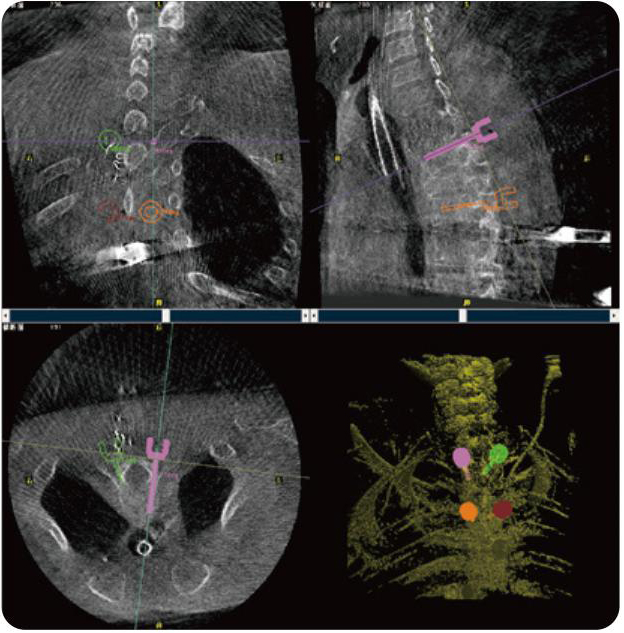

Clinical picture

临床图片